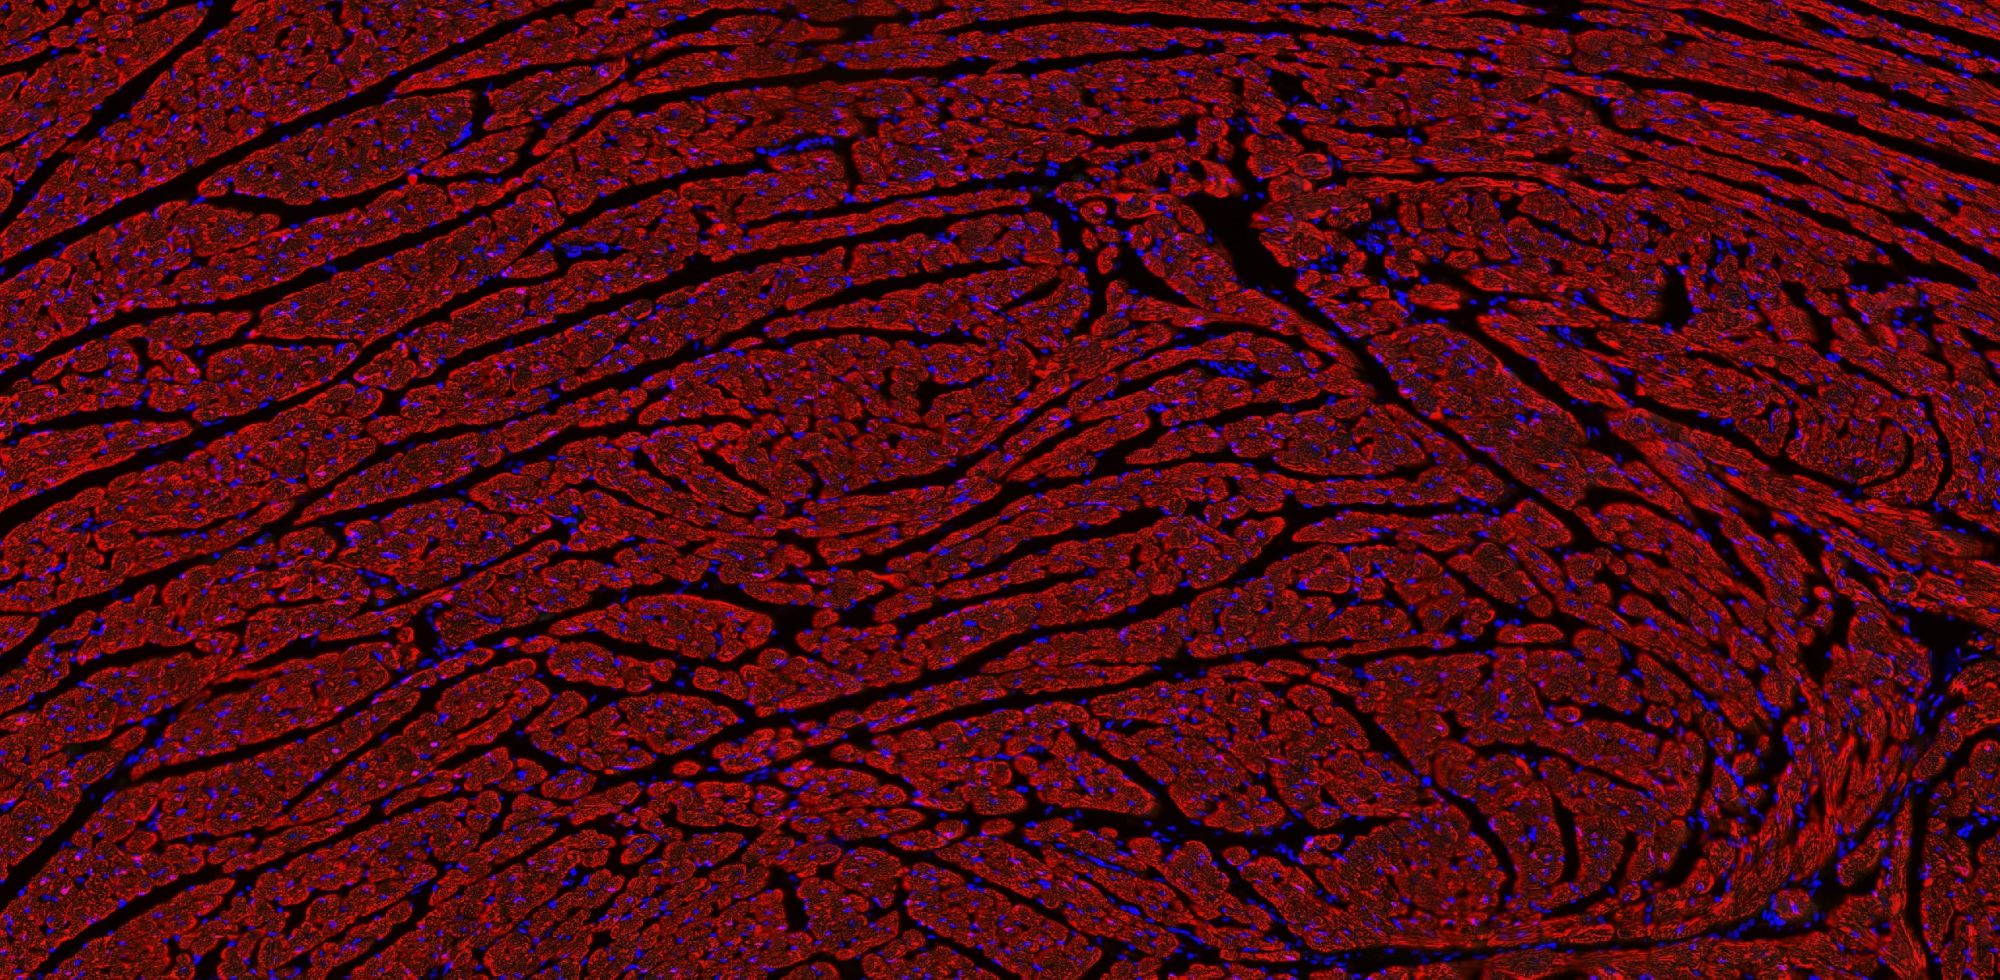

免疫熒光/IF

免疫學(xué)的基本反應(yīng)是抗原-抗體反應(yīng)。由于抗原抗體反應(yīng)具有高度的特異性,所以當(dāng)抗原抗體發(fā)生反應(yīng)時,只要知道其中的一個因素,就可以查出另一個因素。免疫熒光技術(shù)就是將不影響抗原抗體活性的熒光色素標(biāo)記在抗體(或抗原)上,與其相應(yīng)的抗原(或抗體)結(jié)合后,在熒光顯微鏡下呈現(xiàn)一種特異性熒光反應(yīng)。

【技術(shù)原理】